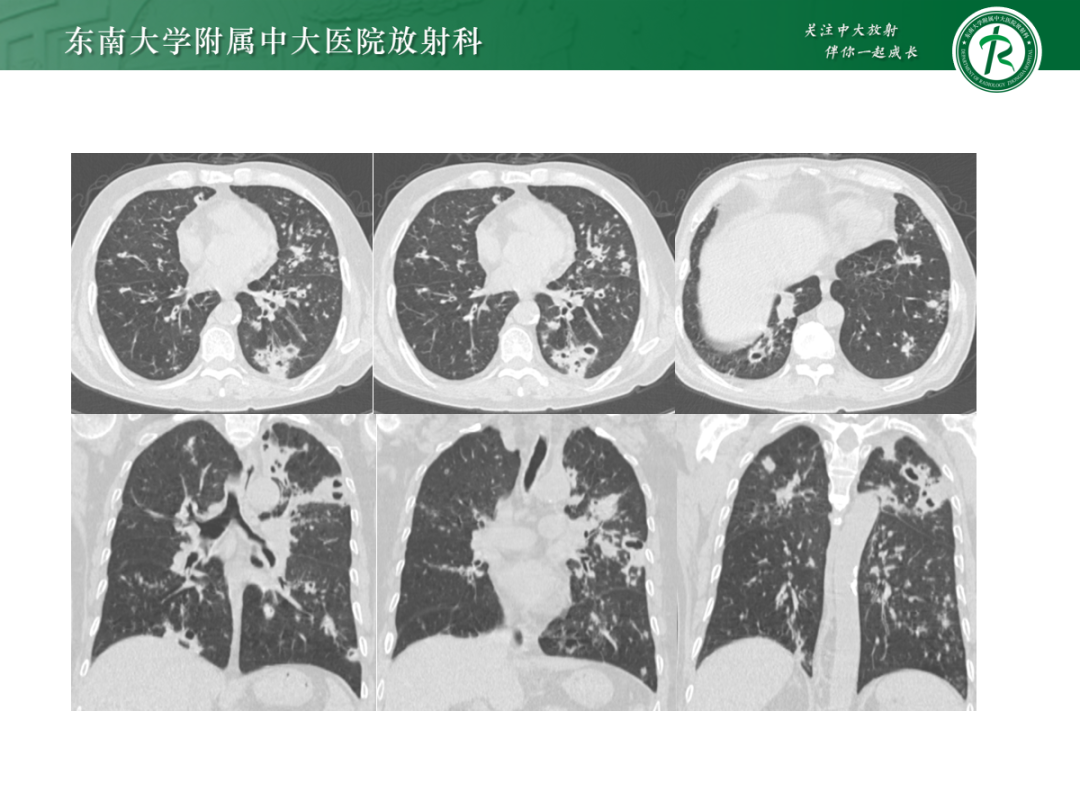

• 病例1:鸟型分枝杆菌复合体肺病

• 病例2:肺诺卡菌病

• 病例3:肺结核

• 病例4:气道侵袭性肺曲霉菌病

影像诊断思路